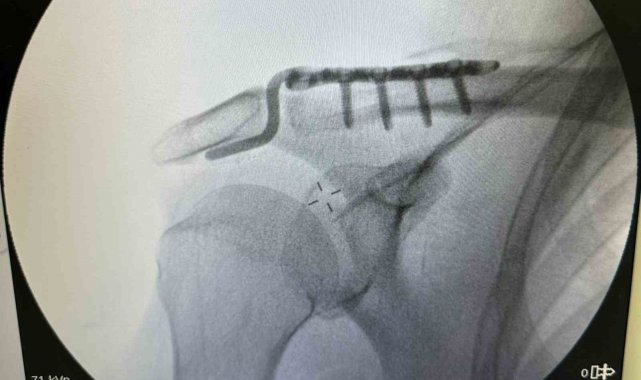

Dr. Başer, hastanın 64 yaşında omuz çıkığı nedeniyle kendilerine başvurduğunu söyledi. Kendisi, arkadaşlarıyla tenis oynarken omuz üzerine düşme sonrası omuzunda bir çıkık geliştiğini belirten Başer, "Normalde bu omuz çıkığını genç hasta grubunda görebiliyoruz. Hastamız ileri yaş olmasına rağmen aktif spor yapan bir hastamız. Bize başvurduğunda omuz eklemi yerinde değildi. Hastanın kemik yapısına tam uyumlu, nadir kullanılan özel bir plak ile başarılı bir ameliyat gerçekleştirdik. Daha sonra biz de ameliyat kararı verdik. Ameliyatında daha çok gençlerde kullanılan nadir, özel şekilli, çengel bir plak kullandık. Daha sonra filmlerini de çekip kontrol ettikten sonra hastamızın ameliyatını başarılı bir şekilde tamamladık. Başarılı ameliyatın ardından hemen fizik tedavi sürecini başlattık. Hastamız bugünden itibaren yavaş yavaş omuz hareketlerini yapabilecek hale geldi. Kol askısından bir an önce kurtulacak ve hastamız en geç 2-3 haftaya kadar eski omuz hareketlerine ağrısız kavuşmasını bekliyoruz" dedi.

Daha önce başvurduğu doktorların ileri yaşı nedeniyle ameliyatın mümkün olmayacağını ve kendiliğinden iyileşmesi gerektiğini söylediklerini belirten Rençber ise, "Benim gibi emekli olan arkadaşlarımla tenis oynarken omuz üstüne düştüm. Düşmem münasebetiyle omuzdaki açılma çok büyüktü. Birkaç doktora gittim ve Bu ameliyatın mümkün olamayacağını, 25 yaşına kadar olan hastaları genelde ameliyat yaptıklarını söylediler. 'Yaşının ileri yaş grubunda olduğunuz için dokunmuyoruz. O kendi kendine iyileşir' dediler. Sonra da Doktor Mehmet Yavuz Bey'e geldim. Mehmet Yavuz Bey durumu inceledi. Dedi ki, 'yapabilirim.' Bunda inşallah sıkıntı yaşamasın dedi şimdi başarılı bir ameliyat oldum, çok memnun kaldım. Bayağı ilgilendi. Ameliyat sonrası en ufak bir sancı, bir sıkıntı görmedim ve yaşamadım. Ameliyat sonrası bile omuzum neredeyse eskisi gibi hareket edebiliyorum, kısıtlılığım ilk gün bile ciddi şekilde azaldı" şeklinde konuştu.